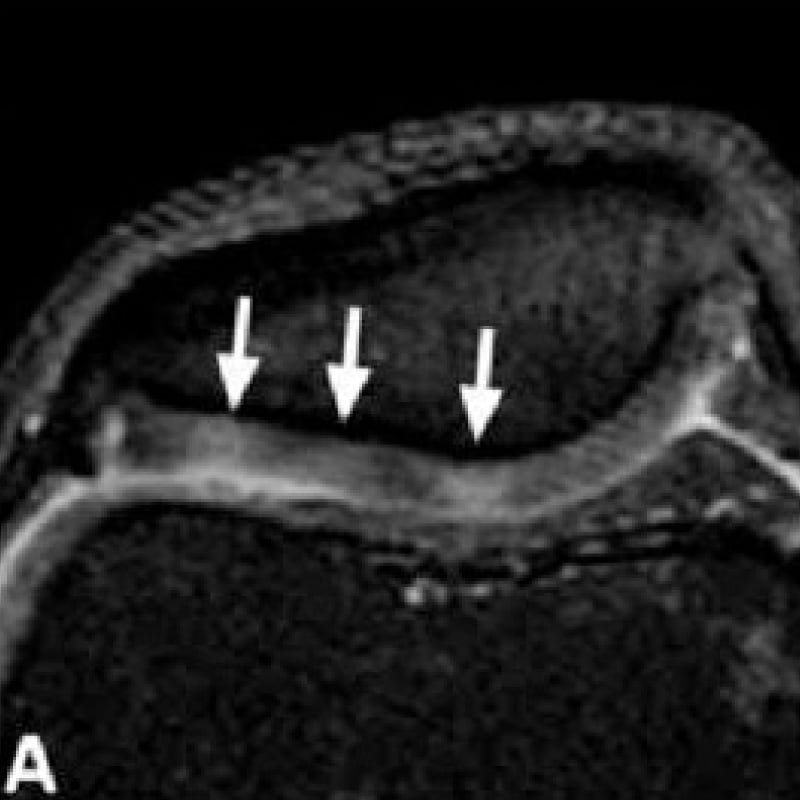

CHONDROMALACIA PATELLA FEMORAL TROCHLEAR CARTILAGE MRI KNEE Radedasia Chondromalacia Patella X-Ray An ap view of the patellofemoral joint is needed to detect any radiological change. Chondromalacia patellae is a condition where there is damaged cartilage behind the patella (kneecap). It is like a softening or. Idiopathic chondromalacia patellae is a condition characterized by idiopathic articular changes of the patella leading to anterior knee. The classification was initially devised for chondromalacia patella. Chondromalacia Patella X-Ray.

Chondromalacia patellae grades IIIV in various patients. (A) Axial Chondromalacia Patella X-Ray Chondromalacia patellae is a condition where there is damaged cartilage behind the patella (kneecap). Chondromalacia patellae is a condition characterized by softening, fraying, and ulceration of patellar articular cartilage. In all but the most advanced cases, there is no convincing radiological change. Softening or wearing away of the patellar articular cartilage (chondromalacia patella) causes varying degrees of. It is like. Chondromalacia Patella X-Ray.